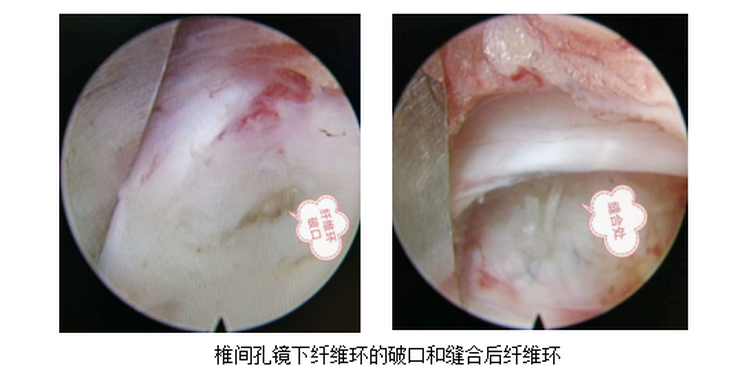

随着骨科技术的发展,腰椎间盘突出症已有很多先进的治疗方法,其中椎间孔镜下髓核摘除术是目前常用的一种行之有效的微创治疗方法。与传统手术相比,该手术具有手术创伤小,对术区周围组织损伤小,出血少,伤口小,可早期下地活动,安全性高等优点。但该手术方式存在术后椎间盘突出疾病复发的可能,为避免术后的再次复发,就需要将患者破损的纤维环进行缝合修复。

6月5日对患者行经椎板入路椎间孔镜下腰5骶1髓核摘除+纤维环修复术治疗。

此次椎间孔镜下纤维环缝合术的开展,有效降低了术后的复发率,使我院脊柱微创手术水平得到再一次提高,标志正我市在脊柱微创诊治领域达到了省级先进水平。